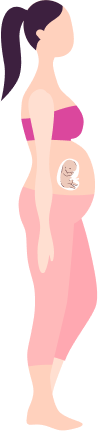

Taking Care of You and Your

Baby Pregnancy Timeline